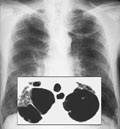

Αθήνα: Αυξημένη κατά 14% είναι η θνησιμότητα από καρκίνο των κατοίκων των Οινοφύτων, σε σχέση με εκείνη των κατοίκων σε όλο τον Νομό Βοιωτίας. Επιστημονική έρευνα δείχνει πως ο καρκίνος ήταν η αιτία θανάτου για έναν στους τέσσερις κατοίκους των Οινοφύτων τα τελευταία 10 χρόνια, γεγονός που ενδέχεται να οφείλεται στο μολυσμένο από εξασθενές χρώμιο νερό.